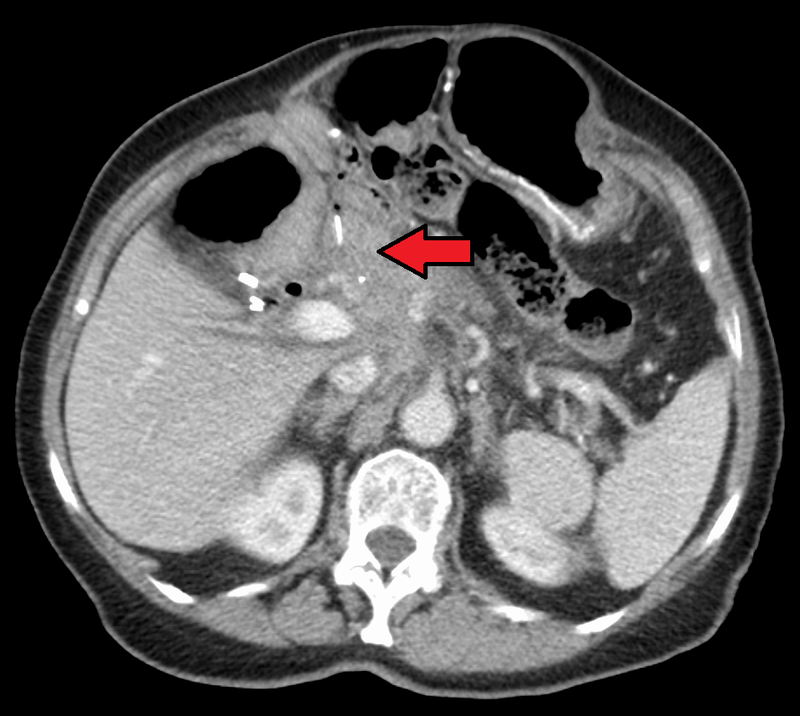

Pancreatic cancer is one of the most aggressive forms of cancers, often with a very poor prognosis. Approximately 11 out of 100,000 men and women per year die from pancreatic cancer in the United States. One of the drugs used in treating pancreatic cancer is nab-paclitaxel. This is a nanoparticle made up of albumin bound to the paclitaxel. It is currently the first line of treatment against pancreatic cancer.

The researchers then went on to discover that the in vitro macropinocytosis of the nanoparticle led to the activation of the macrophages. This process was dependent on Toll-like receptor 4 as shown in previously studies on paclitaxel. To validate these findings in vivo the researchers used mouse models of pancreatic cancer. They found that the drug was able to activate pancreatic tumor-associated macrophages.